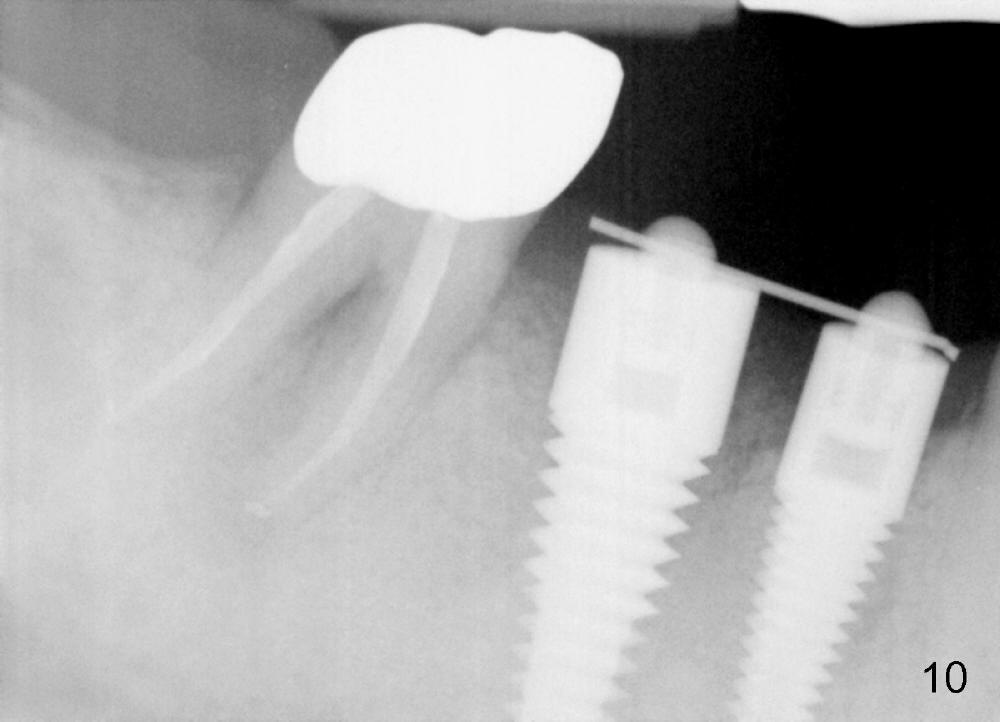

One month after implant placement at the sites of #29,30, the former is found loose (Fig.1,2). It is placed higher than #30. Three weeks later, PA is retaken to confirm that there is space apical to the implant at #29 (Fig.3 double arrows) and that there is distance from the mental loop (yellow dashed line). After infiltration anesthesia, the implant is torqued down initially (compare Fig.4,5) and more (Fig.6,7). To prevent re-loosening, the two implants are splinted (Fig.8).

In 3 months, the gingiva appears to have grown up to cover more of the most coronal portion of the implants (Fig.9). Since the tooth #31 becomes symptomatic probably due to overloading (Fig.10), these 2 implants are prepared for restoration ahead of time.